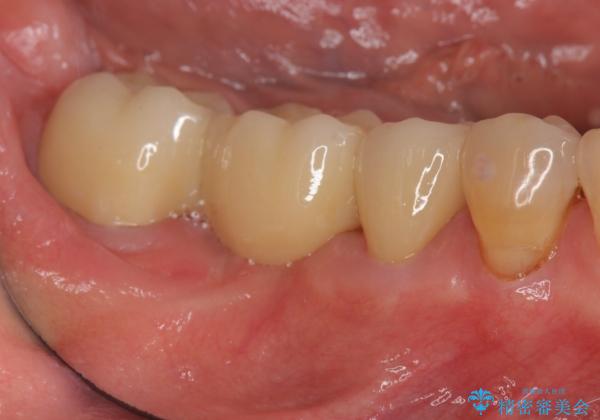

ブリッジが長く機能できるように噛み合わせの微細な調整は非常に大切ですが、支台となる歯の神経を温存できるかどうかも非常に大きな要因です。

今回の治療ではブリッジ製作に先んじて小矯正を行うことで、より予知性を高める治療をおこなうことができました。